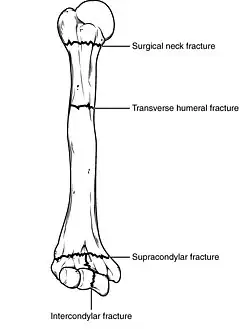

Types of major humerus fractures

Fractures of the humerus are classified based on the location of the fracture and then by the type of fracture. There are three locations that humerus fractures occur: at the proximal location, which is the top of the humerus near the shoulder, in the middle, which is at the shaft of the humerus, and the distal location, which is the bottom of the humerus near the elbow.[9] Proximal fractures are classified into one of four types of fractures based on the displacement of the greater tubercle, the lesser tubercle, the surgical neck, and the anatomical neck, which are the four parts of the proximal humerus, with fracture displacement being defined as at least one centimeter of separation or an angulation greater than 45 degrees. One-part fractures involve no displacement of any parts of the humerus, two-part fractures have one part displaced relative to the other three; three-part fractures have two displaced fragments, and four-part fractures have all fragments displaced from each other.[13][14][3] Fractures of the humerus shaft are subdivided into transverse fractures, spiral fractures, "butterfly" fractures, which are a combination of transverse and spiral fractures, and pathological fractures, which are fractures caused by medical conditions.[12] Distal fractures are split between supracondylar fractures, which are transverse fractures above the two condyles at the bottom of the humerus, and intercondylar fractures, which involve a T- or Y-shaped fracture that splits the condyles.[7]